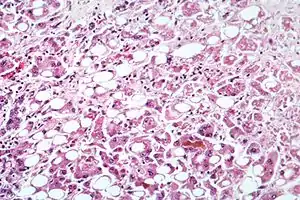

![]() Мікрофотографія клітин печінки при хронічному алкогольному стеатогепатиті (один з варіантів перебігу алкогольної хвороби печінки) Мікрофотографія клітин печінки при хронічному алкогольному стеатогепатиті (один з варіантів перебігу алкогольної хвороби печінки) | |